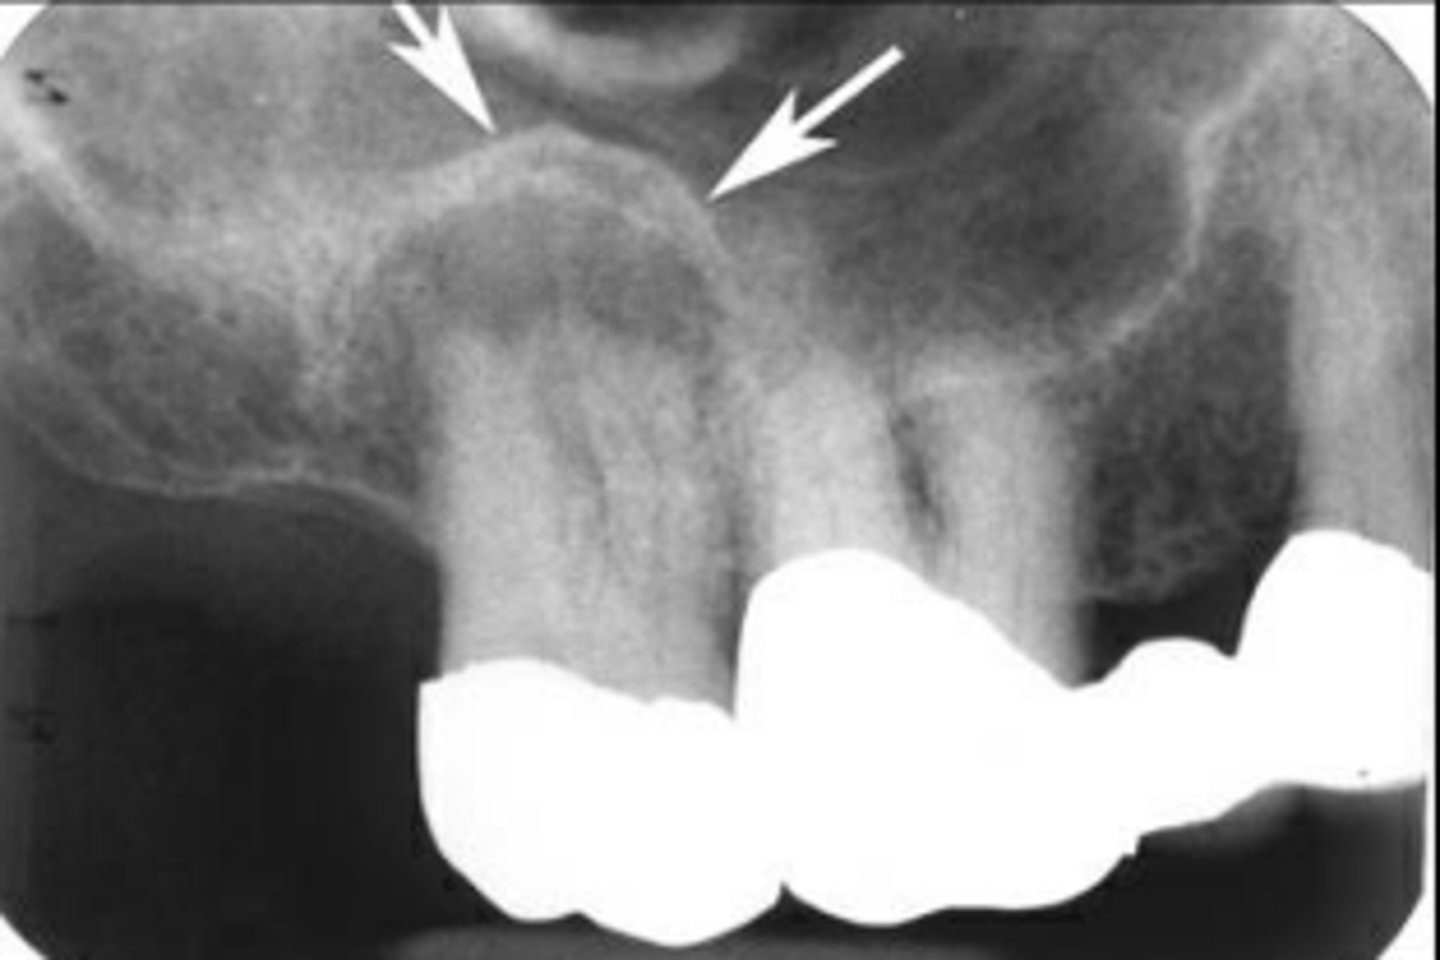

What area does odontogenic keratocyst (OKC) expand?

Mandibular posterior area

How does odontogenic keratocyst (OKC) expand around teeth?

Around entire tooth

What is the recurrence rate of odontogenic keratocyst (OKC)?

High recurrence rate

What are the differential diagnoses for odontogenic keratocyst (OKC)?

Ameloblastoma, dangerous cyst